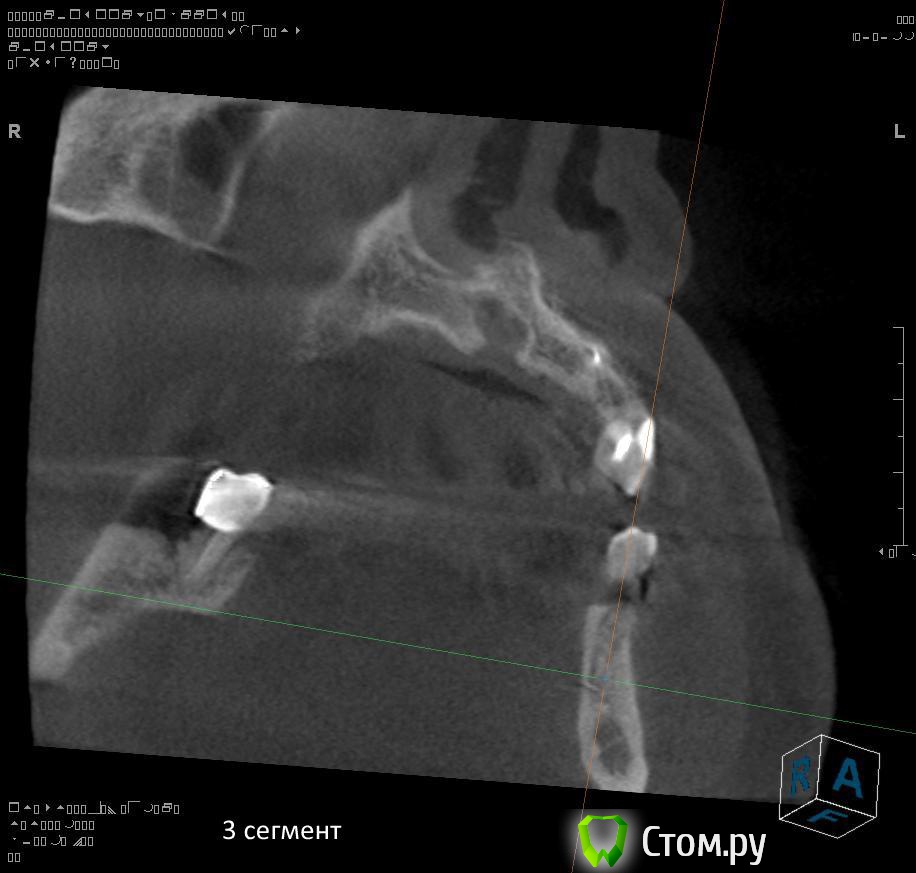

4. через 1,5 - 2 месяца после удаления 4.4 и 4.7 провести установку имплантатов в 4 сегменте?

5. в какие позиции должны быть поставлены имплантаты в 4 сегменте сбоку (4.5, 4.7?)?

6. через какой промежуток времени после удаления зубов 3.4, 3.5 проводить аугментацию в 3 сегменте? какая аугментация предпочтительнее? в какие позиции должны быть поставлены имплантаты (3.4, 3.6?)?